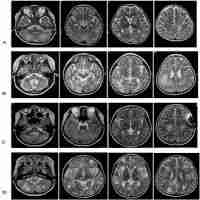

| Abstract | Familial hemophagocytic lymphohistiocytosis (FHL), is a rare autosomal recessive disorder characterized by an impairment of cytotoxic cells and uncontrolled activation of macrophages. This study presents the first description of four patients with FHL type 2 in Latin America. Patient 1 fulfilled the disease diagnostic criteria since 2 months of age, whereas patients 2, 3 and 4 exhibited the typical manifestations of the disease only later in their childhood. The PRF1 genetic analysis in these patients revealed two previously reported mutations: L17fsx50 and R54C. Interestingly, seven out of the 8 alleles evaluated here in patients carried the haplotype R54C/A91V, suggesting that this is a highly frequent FHL type 2 allele in Colombia. This haplotype confers residual cytotoxic function leading to late onset disease. Therefore, this report highlights the remarkable complexity of FHL diagnostic, emphasizing the importance of the genetic characterization of the disease. |